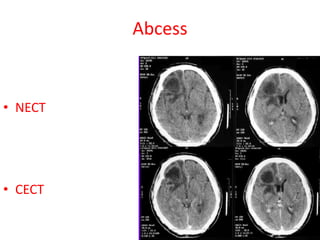

Abcess

• NECT

• CECT